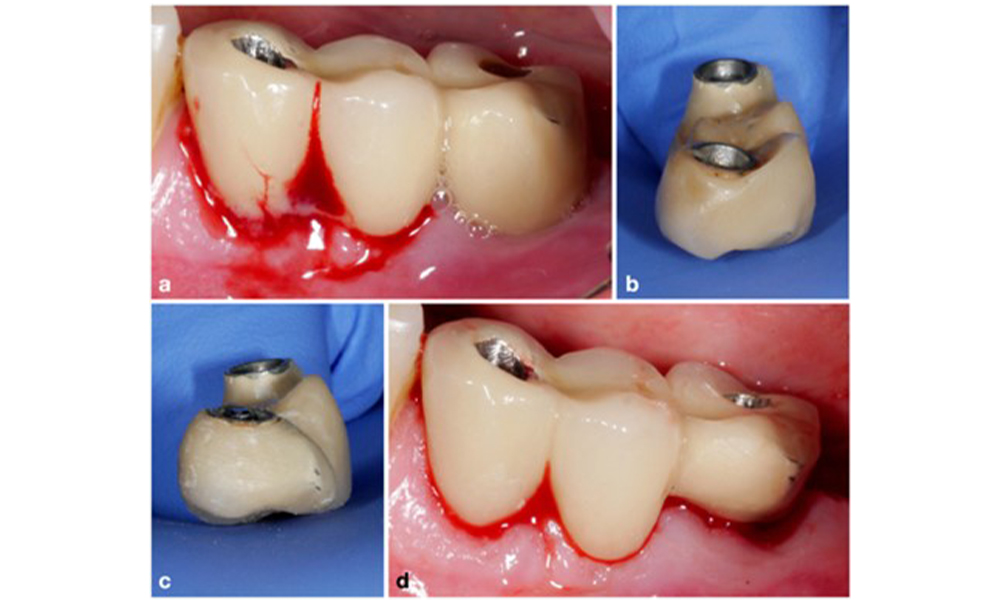

Defect extent, implant position, and its strategic importance determine whether an implant can or should be treated. Similar to a non-treatable (hopeless) implant, a severely affected implant in a multiple-unit restoration may be irrelevant for treatment, as its loss does not compromise the prosthetic restoration. Consequently, it is advisable to consider explantation either upon diagnosis or during surgical intervention (figure 8).

Explantation of a severely affected implant using a piezo surgery device. The implant in position 43 was part of a 4-unit bridge supported by 3 implants. Because of significant bone loss and minor relevance in the support for the bridge, treating the implant was deemed impractical. Explantation was performed with a piezo surgery device and specially designed tips (a-c) ensuring a minimal amount of bone loss (d).

Figure 8. Explantation of a severely affected implant using a piezo surgery device. The implant in position 43 was part of a 4-unit bridge supported by 3 implants. Because of significant bone loss and minor relevance in the support for the bridge, treating the implant was deemed impractical. Explantation was performed with a piezo surgery device and specially designed tips (a-c) ensuring a minimal amount of bone loss (d).